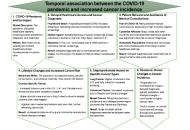

This article belongs to the special issue Advances in Oral Cancer: Prevention, Diagnosis, and Therapeutics The viral oncogenesis of COVID-19 and its impact on cancer progression, long-term risks, treatment complexities, and research strategiesOpen AccessReviewThe interaction between cancer and coronavirus disease 2019 (COVID-19) poses significant challenges, particularly for immunocompromised individuals who are at heightened risk for acute infections an [...] Read more.Moawiah M Naffaa, Ola A Al-EwaidatPublished: April 28, 2025 Explor Med. 2025;6:1001314

The viral oncogenesis of COVID-19 and its impact on cancer progression, long-term risks, treatment complexities, and research strategiesOpen AccessReviewThe interaction between cancer and coronavirus disease 2019 (COVID-19) poses significant challenges, particularly for immunocompromised individuals who are at heightened risk for acute infections an [...] Read more.Moawiah M Naffaa, Ola A Al-EwaidatPublished: April 28, 2025 Explor Med. 2025;6:1001314